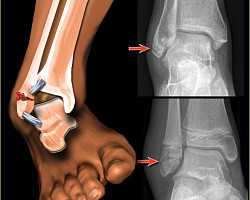

В клинической практике переломы одной лодыжки называют однолодыжечными, переломы обеих лодыжек (внутренней и наружной) - двухлодыжечными, переломы обеих лодыжек и переднего или заднего края большеберцовой кости - трехлодыжечными. Одно- и двухлодыжечные повреждения в 50-70% случаев не сопровождаются смещением фрагментов. Трехлодыжечные переломы относятся к категории тяжелых повреждений, при них, как правило, наблюдается выраженное смещение, расхождение вилки голеностопного сустава, подвывих и разрыв связок.

При переломах со смещением сустав сильно отечен, деформирован. Кожа с синюшным или багровым оттенком, имеются выраженные кровоподтеки, иногда распространяющиеся на тыл стопы и подошву. Лодыжки не контурируются из-за отека. Между голенью и стопой образуется угол, открытый кнаружи или кнутри (в зависимости от вида подвывиха). Отмечается патологическая подвижность, в некоторых случаях определяется крепитация. Движения и опора невозможны из-за боли.

Переломы лодыжек следует дифференцировать с повреждением связок голеностопного сустава. При переломах боль, как правило, локализуется выше, максимальная болезненность определяется при пальпации костей, а не мягкотканных образований. Для постановки окончательного диагноза назначается рентгенография голеностопного сустава в двух стандартных проекциях (боковой и переднезадней). На снимках определяются линии изломов, направление и степень смещения отломков, вид подвывиха и степень расхождения берцовых костей. В сомнительных случаях назначают КТ голеностопного сустава, при необходимости оценить состояние мягкотканных структур - МРТ голеностопного сустава.